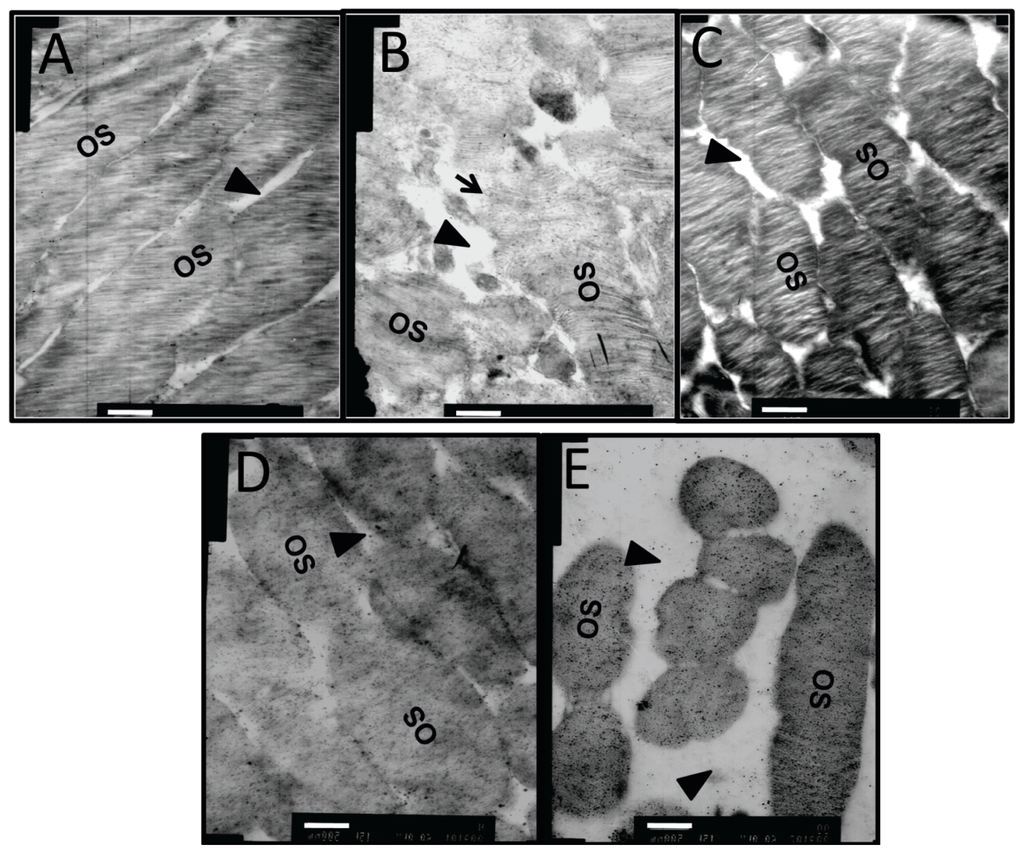

In the retina of normal controls (Figure 7A), the capillary lumen (black triangle) was smooth and intact, with red blood cells passing through. The thin sheath of endothelial cells (black arrow) closely attached to the continuous base membrane. The photoreceptor outer segments (OS) were intact and organized with little space (black triangle) between them (Figure 8A). In diabetic retinas without intervention, heterochromatin margination (white arrow), kidney-shaped swelled nucleus, and multiple secondary lysosomes were observed in microvessel endothelial cells (black arrow), and retinal capillary lumen was narrowed and ill-defined (Figure 7B). The organization of OS was disrupted, the gap between OS became larger (black triangle), and some structures of the OS were blurred due to breakage and dissolution of membrane discs (black arrow) (Figure 8B). Notably, the capillary lumen (black triangle) in retina of the dual-target intervention group (Figure 7C) was unobstructed, in which passing red blood cells were seen. Endothelial cells (black arrow) in this group were slightly swelled, and pericytes were clear and intact (Figure 7C). Moreover, photoreceptor OS in this group was organized with a discernible structure of the membrane discs, and the inter-OS space was much reduced compared to that in diabetic retina without intervention (black triangle) (Figure 8C). In contrast, stenotic retinal capillary lumen (black triangle) and deformed red blood cells were observed in both single-target intervention groups (Figure 7D,E). Swelled endothelial cells (Figure 7D,E, black arrow), marginalized heterochromatin (Figure 7D,E, white arrow), and loosely organized photoreceptor OS with a blurred membrane disc structure (Figure 8D,E) were also found in the retina of these groups. The TEM results indicate that the ultrastructure of retinal microvessels and photoreceptor OS in the dual-target intervention group were less damaged than the single-target and non-intervention groups, suggesting the greater effectiveness of the dual-target intervention on diabetic retina.

Figure 7.

The ultrastructural changes in retinal microvessels of diabetic rats after dual-target intervention. One week after intervention, the ultrastructure changes of retinal microvessels were examined by TEM in normal controls (A); diabetic rats without intervention (B); diabetic rats subjected to ranibizumab and CTGF shRNA dual-target intervention (C); and diabetic animals subjected to ranibizumab (D) or CTGF shRNA (E) single-target intervention. Representative pictures are shown (n = 5). Black triangles indicate capillary lumen, black arrows indicate endothelial cells, and white arrows indicate heterochromatin. Bm: Basement membrane, Lu: capillary lumen, Ed: endothelial cell; Ly: lysosomes; Pe: pericyte; Mi: mitochondria, N: nucleus, Hc: heterochromatin, RBC: red blood cell. Scale bar = 500 nm.